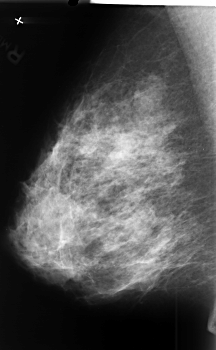

B_3409_1.RIGHT_CC

RIGHT_CC LINES 4576 PIXELS_PER_LINE 2944 BITS_PER_PIXEL 12 RESOLUTION 50 NON_OVERLAY